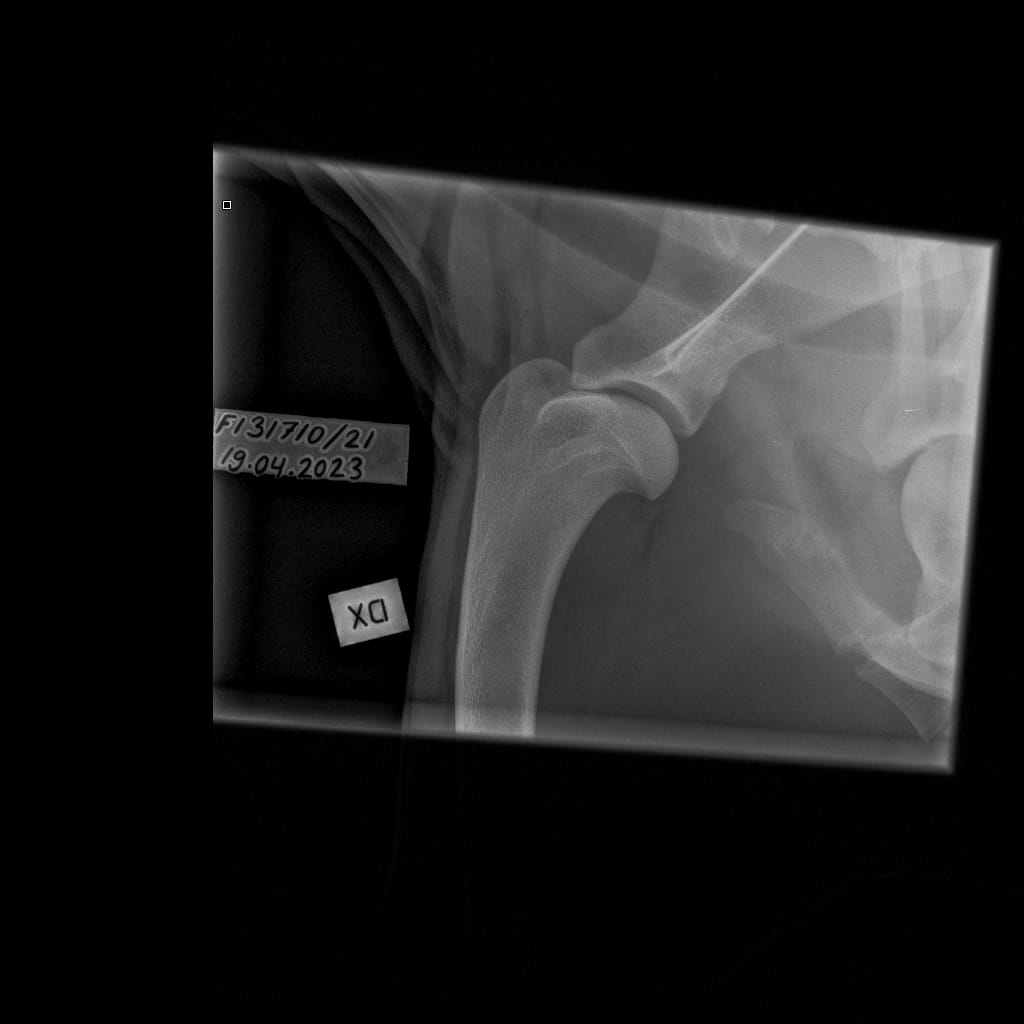

Eturaajat -Olkanivel ML -6.11.2023-16_02_08-264